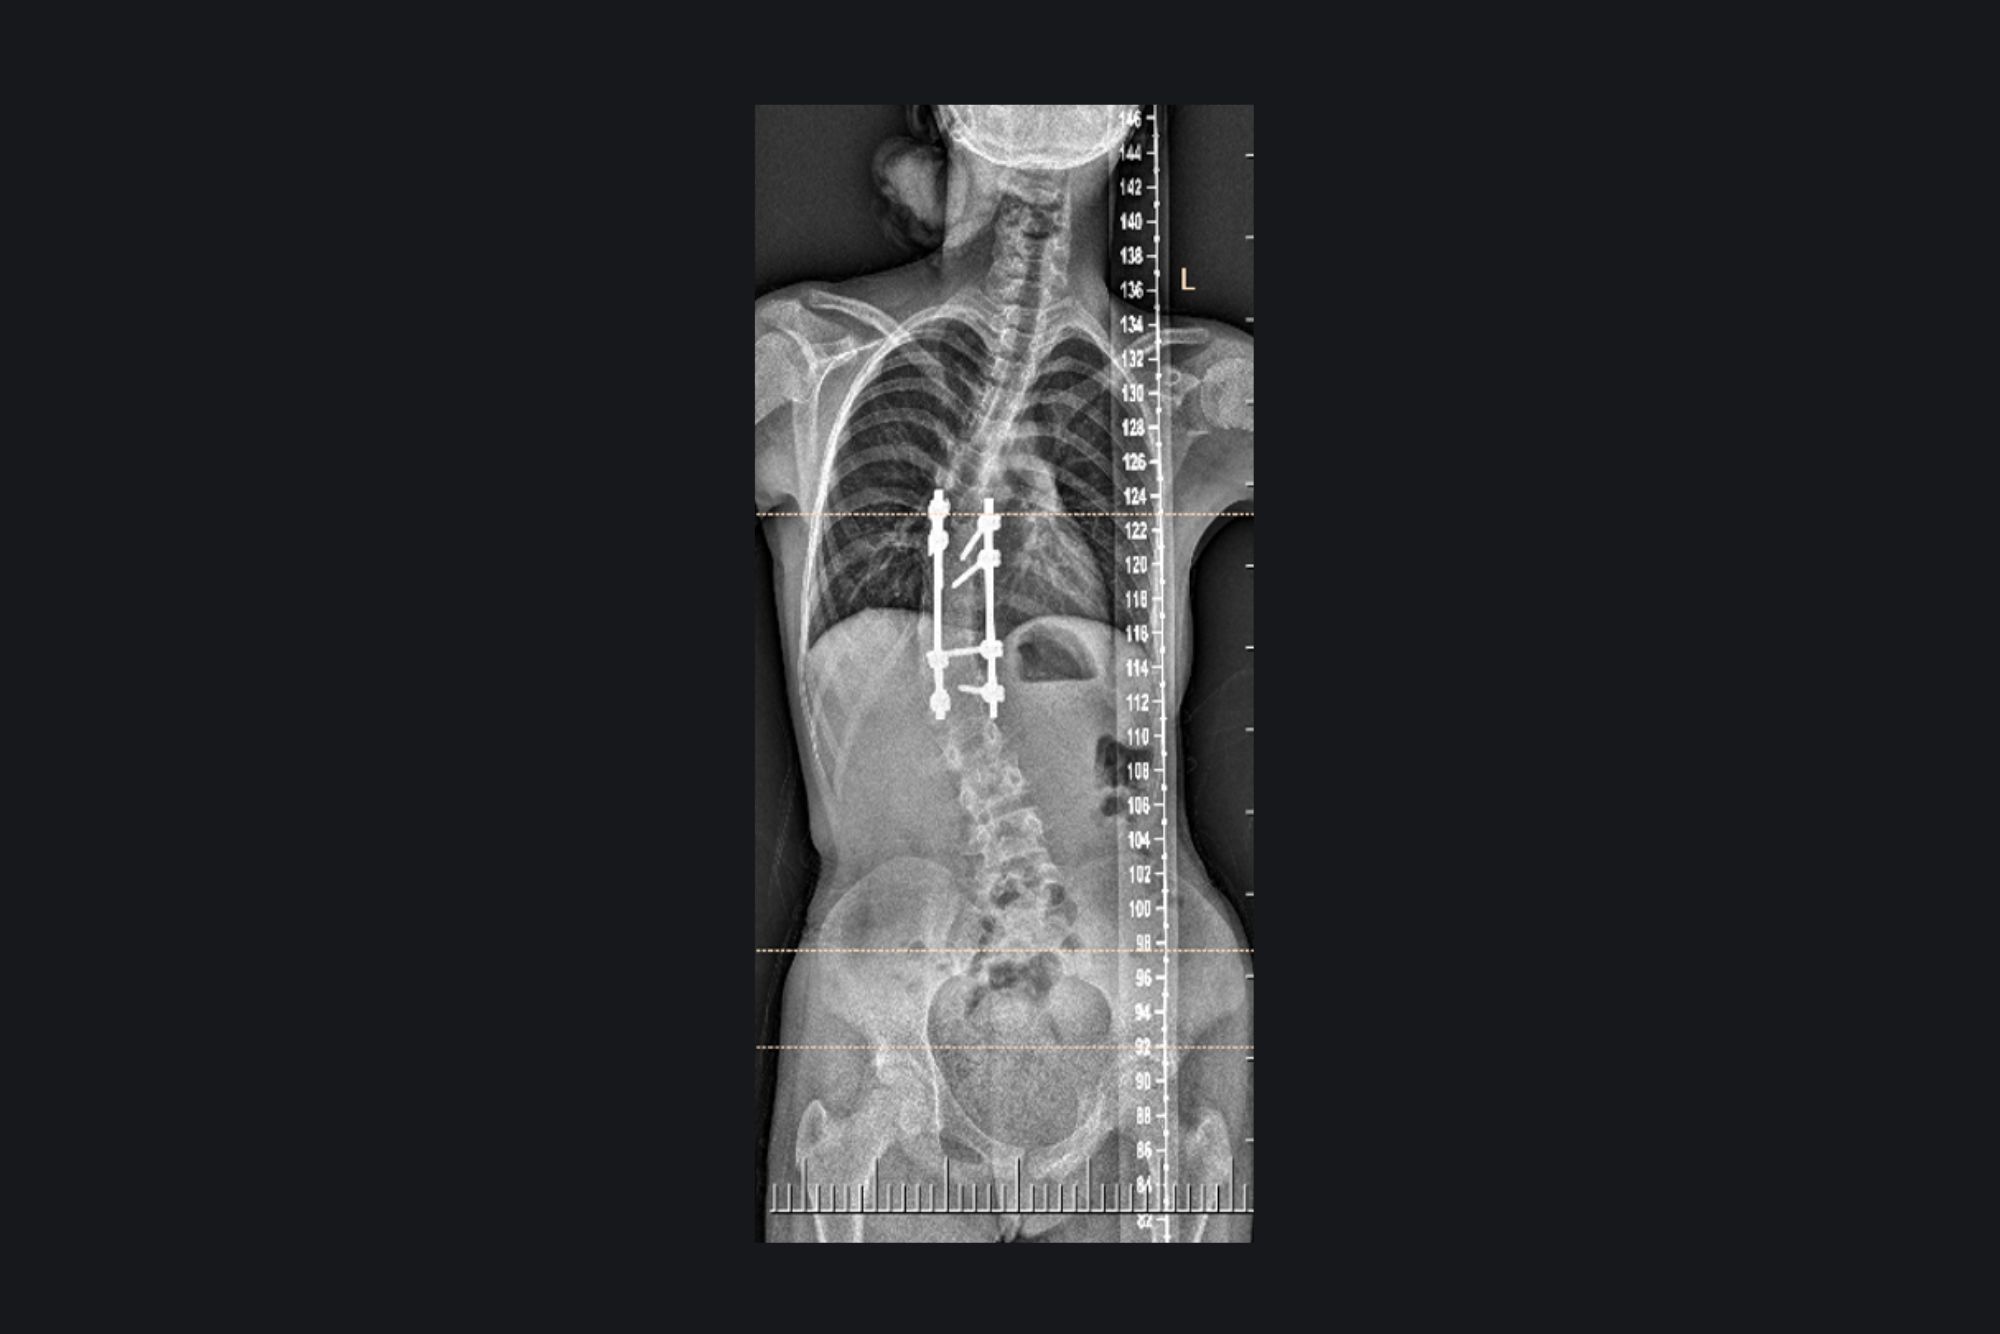

Deformity Of Back

Preoperative MRI

Postoperative MRI